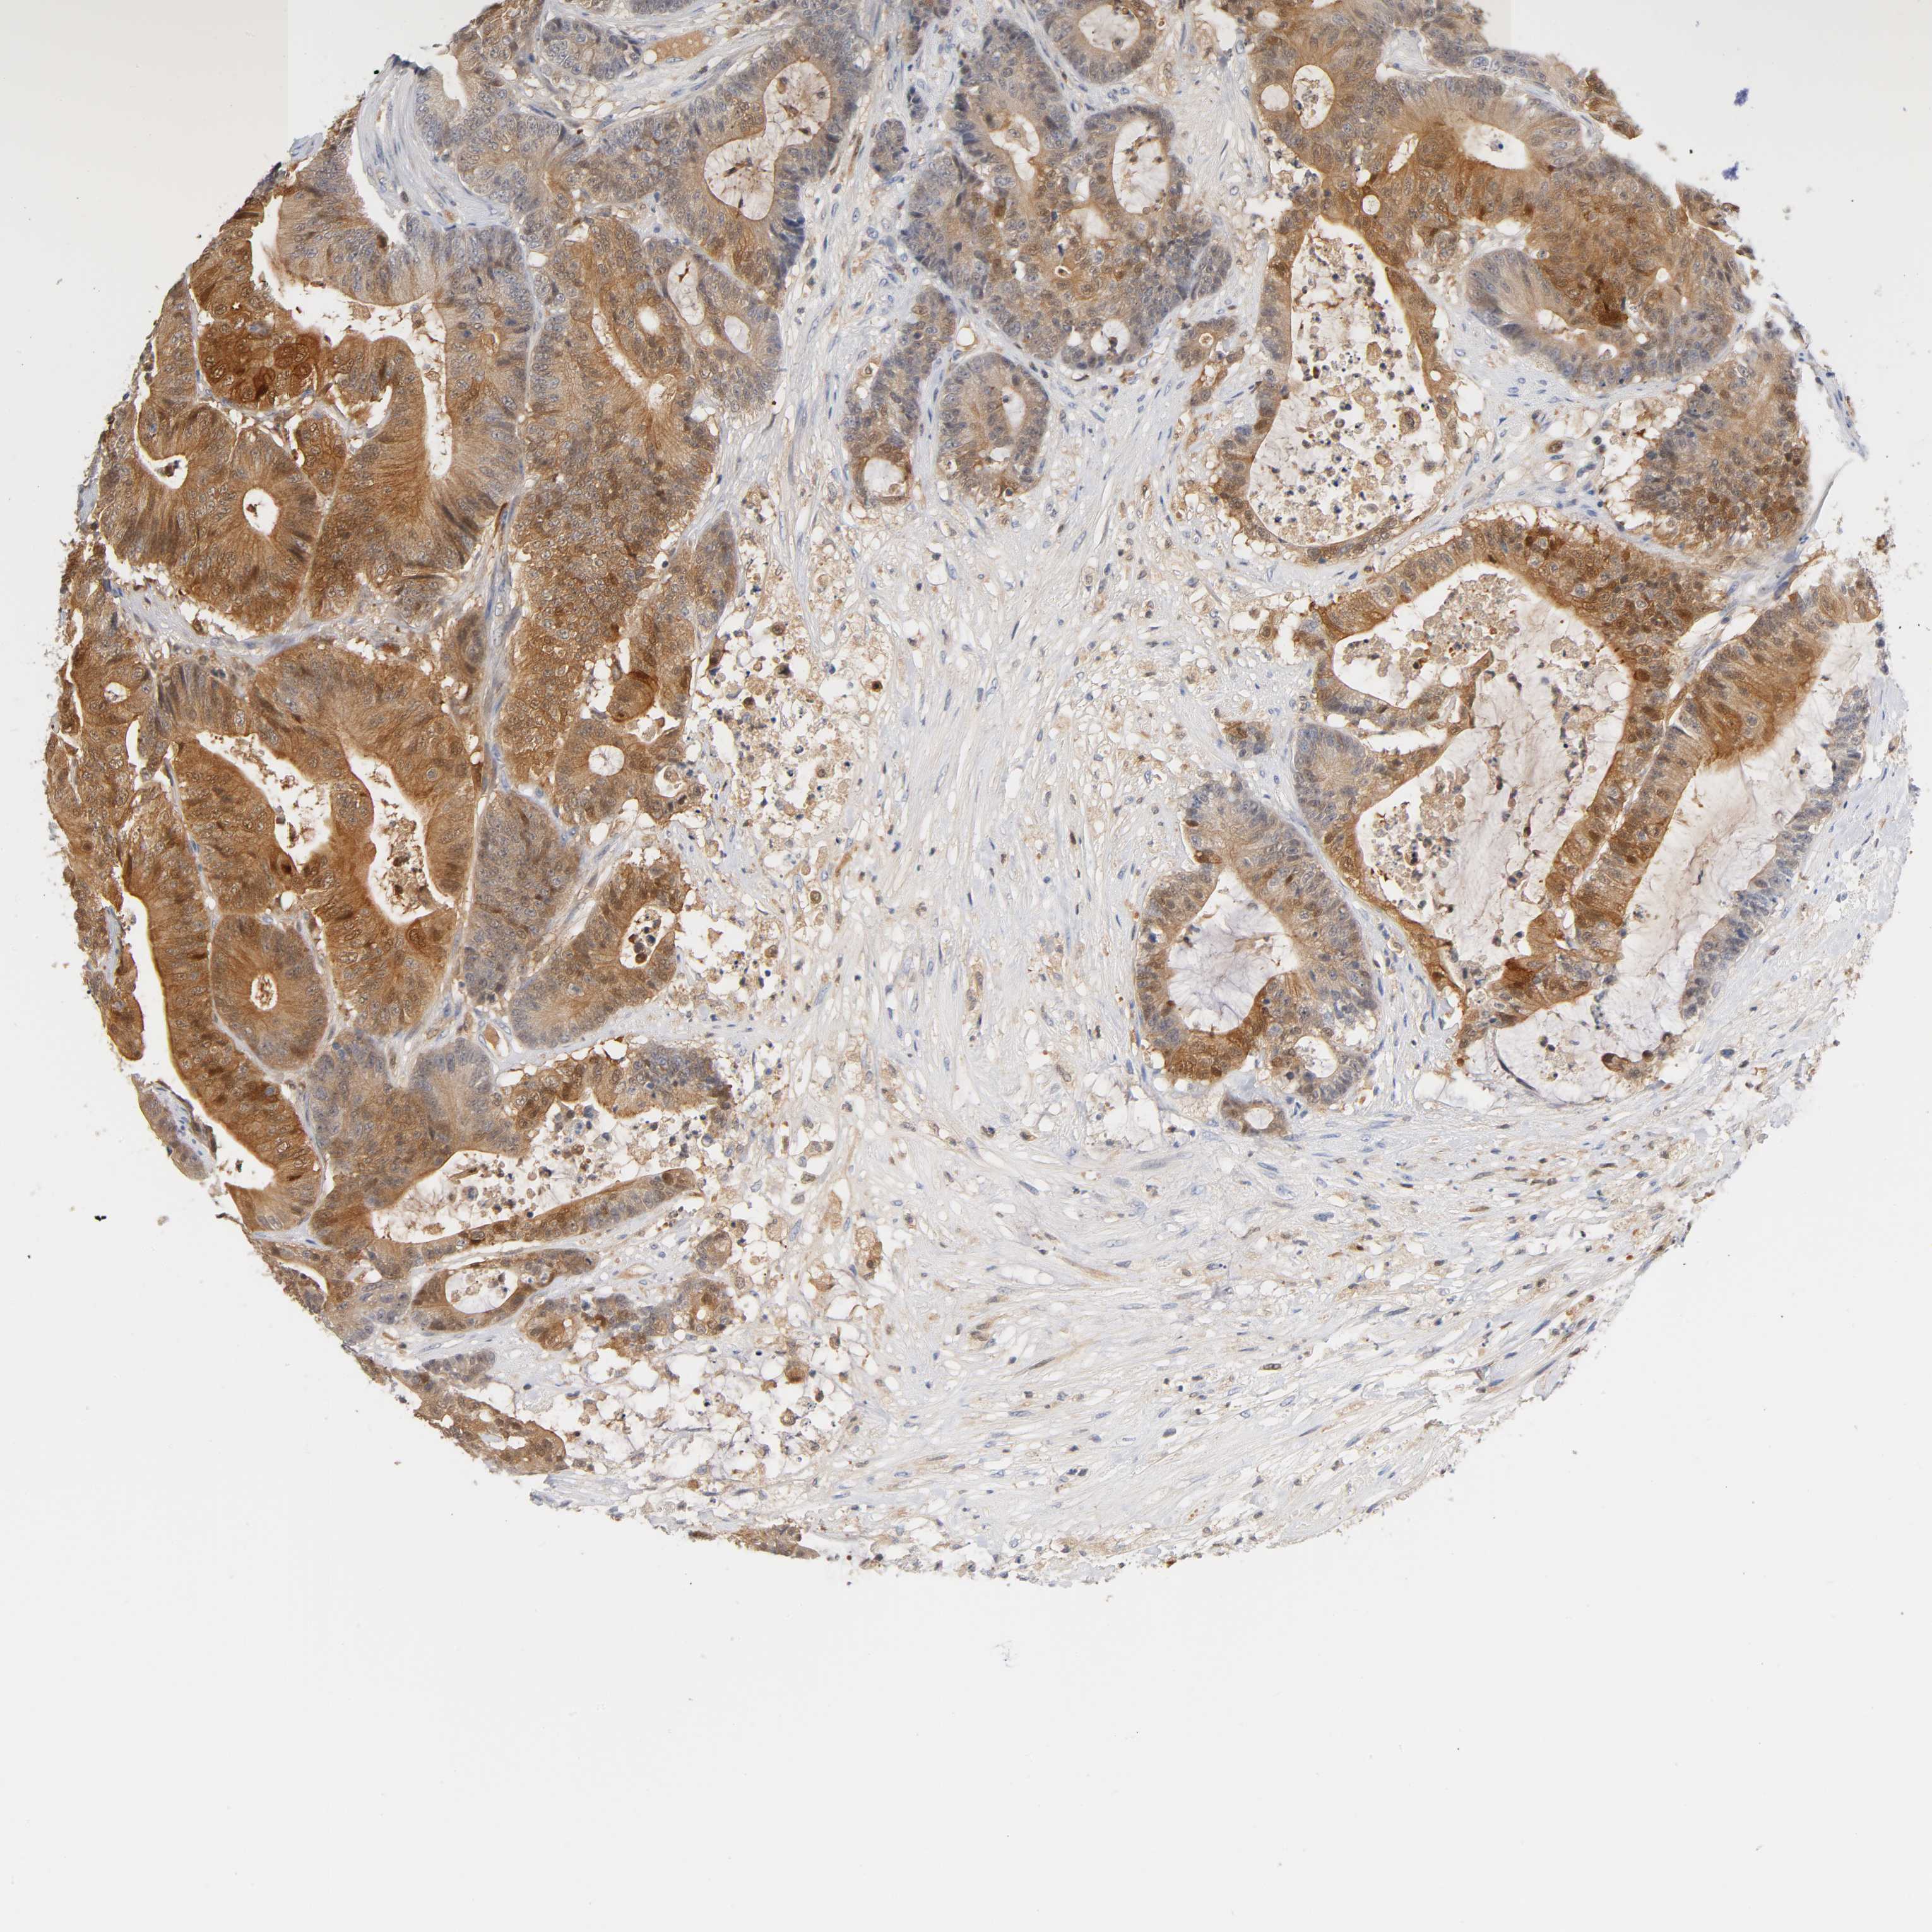

CANCER COLORECTAL CANCER Show tissue menu

Colorectal cancer

Human cancer